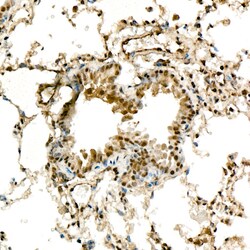

Invitrogen™ METTL4 Recombinant Rabbit Monoclonal Antibody (9N4K4)

| ELISA, Immunohistochemistry (Paraffin) | |